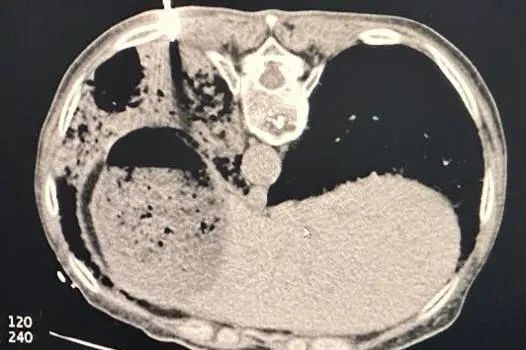

给予高流量氧疗(流量30L/min,氧浓度70%)、改用卡泊芬净进行抗真菌治疗。支气管镜检查显示,患者的气管、隆突、左肺及右肺各级支气管管腔内有大量白色稀薄痰液涌出。尽管进行了积极治疗,但一周后复查胸部CT发现,患者的双肺仍呈“大白肺”样改变,病变范围扩大,密度增加。提示不排除肺水肿可能……

图片

2024-6-26胸部CT影像